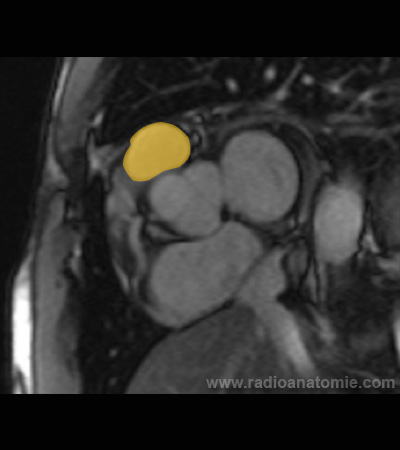

Radioanatomie et plans de coupe en IRM cardiaque

Aorte ascendante